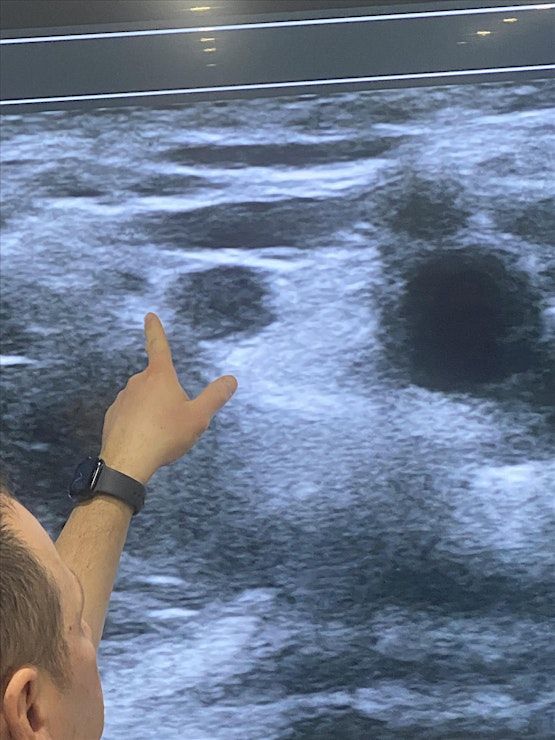

Ultrasound IV Access Workshop

This 1.5 h workshop has been developed for both novices and advanced nurses, PAs and physicians providers who would like to either learn the basic theory and practical aspects of ultrasound guided venous access.. Participants will have up to 30-60min hands on ultrasound scanning on live models and lecture to learn and identify sono‐anatomy as well as practice IV Cannulation on our phantoms. At the end of the workshop, you will be expected to have gained thorough knowledge and immense confidence in the use of ultrasound guided IV placement.

• Identify normal sono‐anatomy of the venous system

• Demonstrate needle insertion techniques for ultrasound guided placement both in‐plane and out‐of‐plane

Live Scanning and Practice

Info: Scan the venous system and practice IV insertion on our ultrasound phantoms/